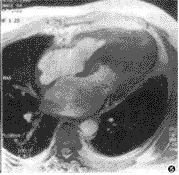

图3 心尖肥厚型心肌病横轴位T1WI示前室间隔及心尖局限性肥厚,左室腔呈桃形

心尖局限性肥厚较为少见,首先由日本学者报道,心电图检查表现为异常Q波、ST-T段及T波改变。右前斜位左心室造影舒张末期呈“桃形心”改变。本组共4例(20%),2例心尖肥厚型心肌病心电图改变显著,但心脏B超未见异常,多角度磁共振平扫及电影均能显示心尖局限肥厚的程度及范围和心腔形态的改变,对明确诊断具有特征性(图3)。与梗阻型肥厚型心肌病相比,心尖肥厚型心肌肥厚程度较轻(2.05±0.31cm),且无左室流出道梗阻。